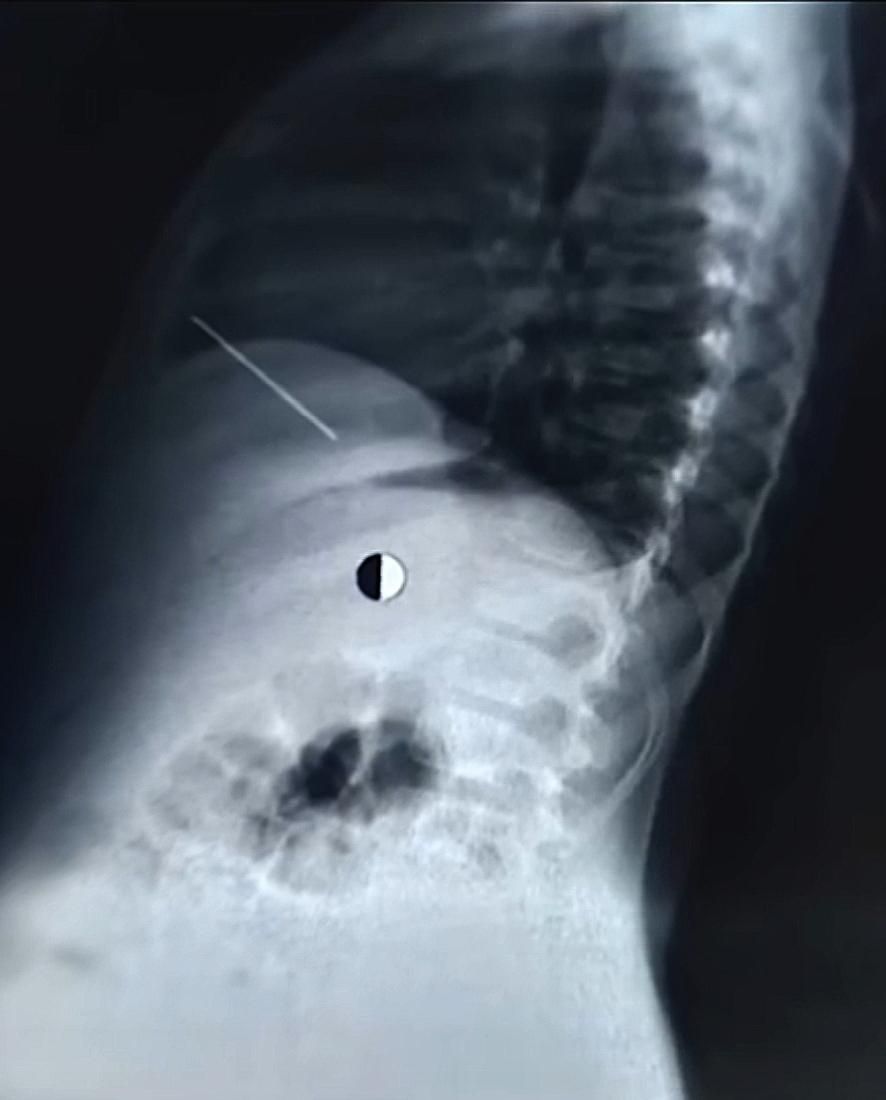

ونجح فريق طبي متخصص من قسم جراحة القلب والصدر في إنقاذ حياة طفل يبلغ من العمر 11 عاماً، حضر إلى المستشفى في حالة حرجة إثر اختراق مسمار "منجد" يبلغ طوله 5 سم لصدره واستقراره مباشرة داخل عضلة القلب، في واقعة طبية حبست الأنفاس وانتهت بانتصار جراحي مصري خالص.

وعلى الفور، تولى الفريق الجراحي بقيادة الدكتور حسام فتحي علي، رئيس وحدة حوادث جراحة القلب والصدر، إجراء عملية استكشاف عاجلة للصدر، حيث تبين وجود تهتك بالرئة اليمنى واختراق المسمار للغشاء التموري وإصابة القلب إصابة مباشرة تسببت في نزيف داخلي حاد حوله، وبمهارة فائقة تم استخراج المسمار وإصلاح التهتكات والسيطرة على النزيف بالكامل.